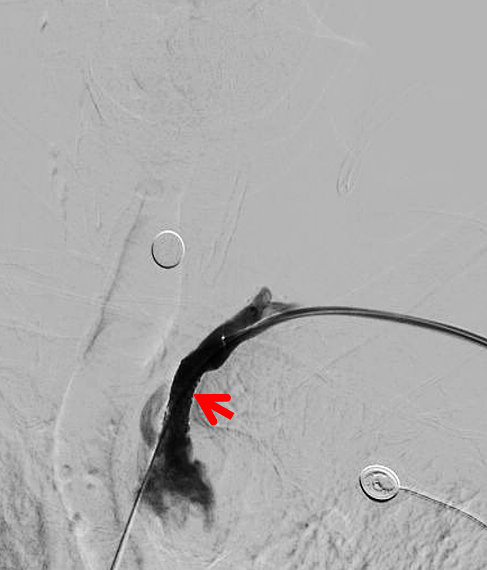

球扩后造影支架成形好,无残余狭窄,椎动脉显影